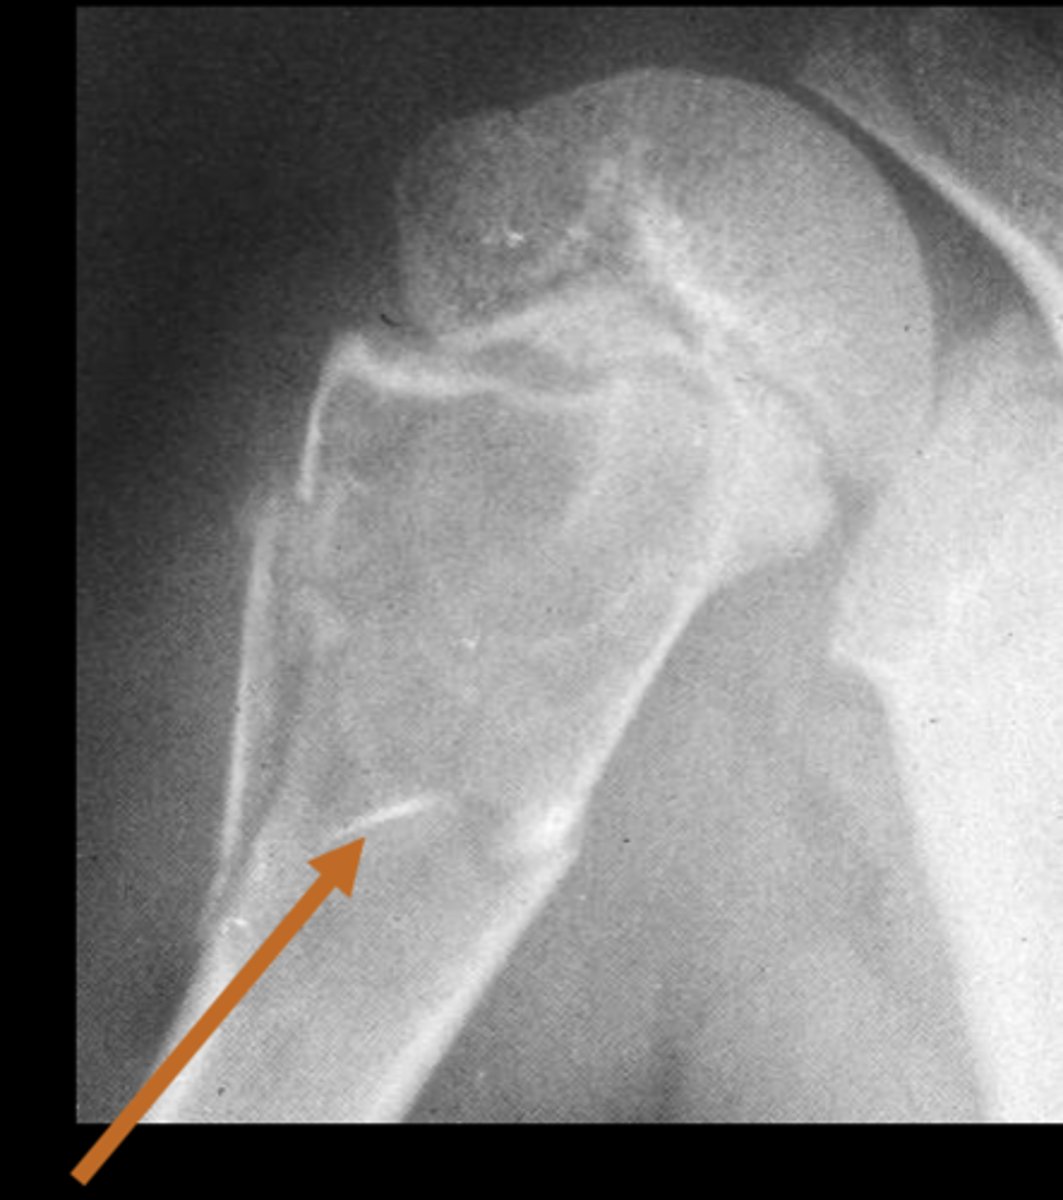

6

New cards

Solitary osteochondroma

- Most common benign skeletal growth or tumor

- 50% of all benign bone tumors

- 10-15% of all primary bone tumors

- 75% <20 y.o.

- M:F, 2:1

- Malignant transformation <1%

<p>- Most common benign skeletal growth or tumor</p><p>- 50% of all benign bone tumors</p><p>- 10-15% of all primary bone tumors</p><p>- 75% &lt;20 y.o.</p><p>- M:F, 2:1</p><p>- Malignant transformation &lt;1%</p>

7

- Mostly asymptomatic

- Painless, hard mass

- Stalk may fracture

- Pain and rapid growth = malignant transformation

State the clinical features of solitary osteochondroma

<p>State the clinical features of solitary osteochondroma</p>